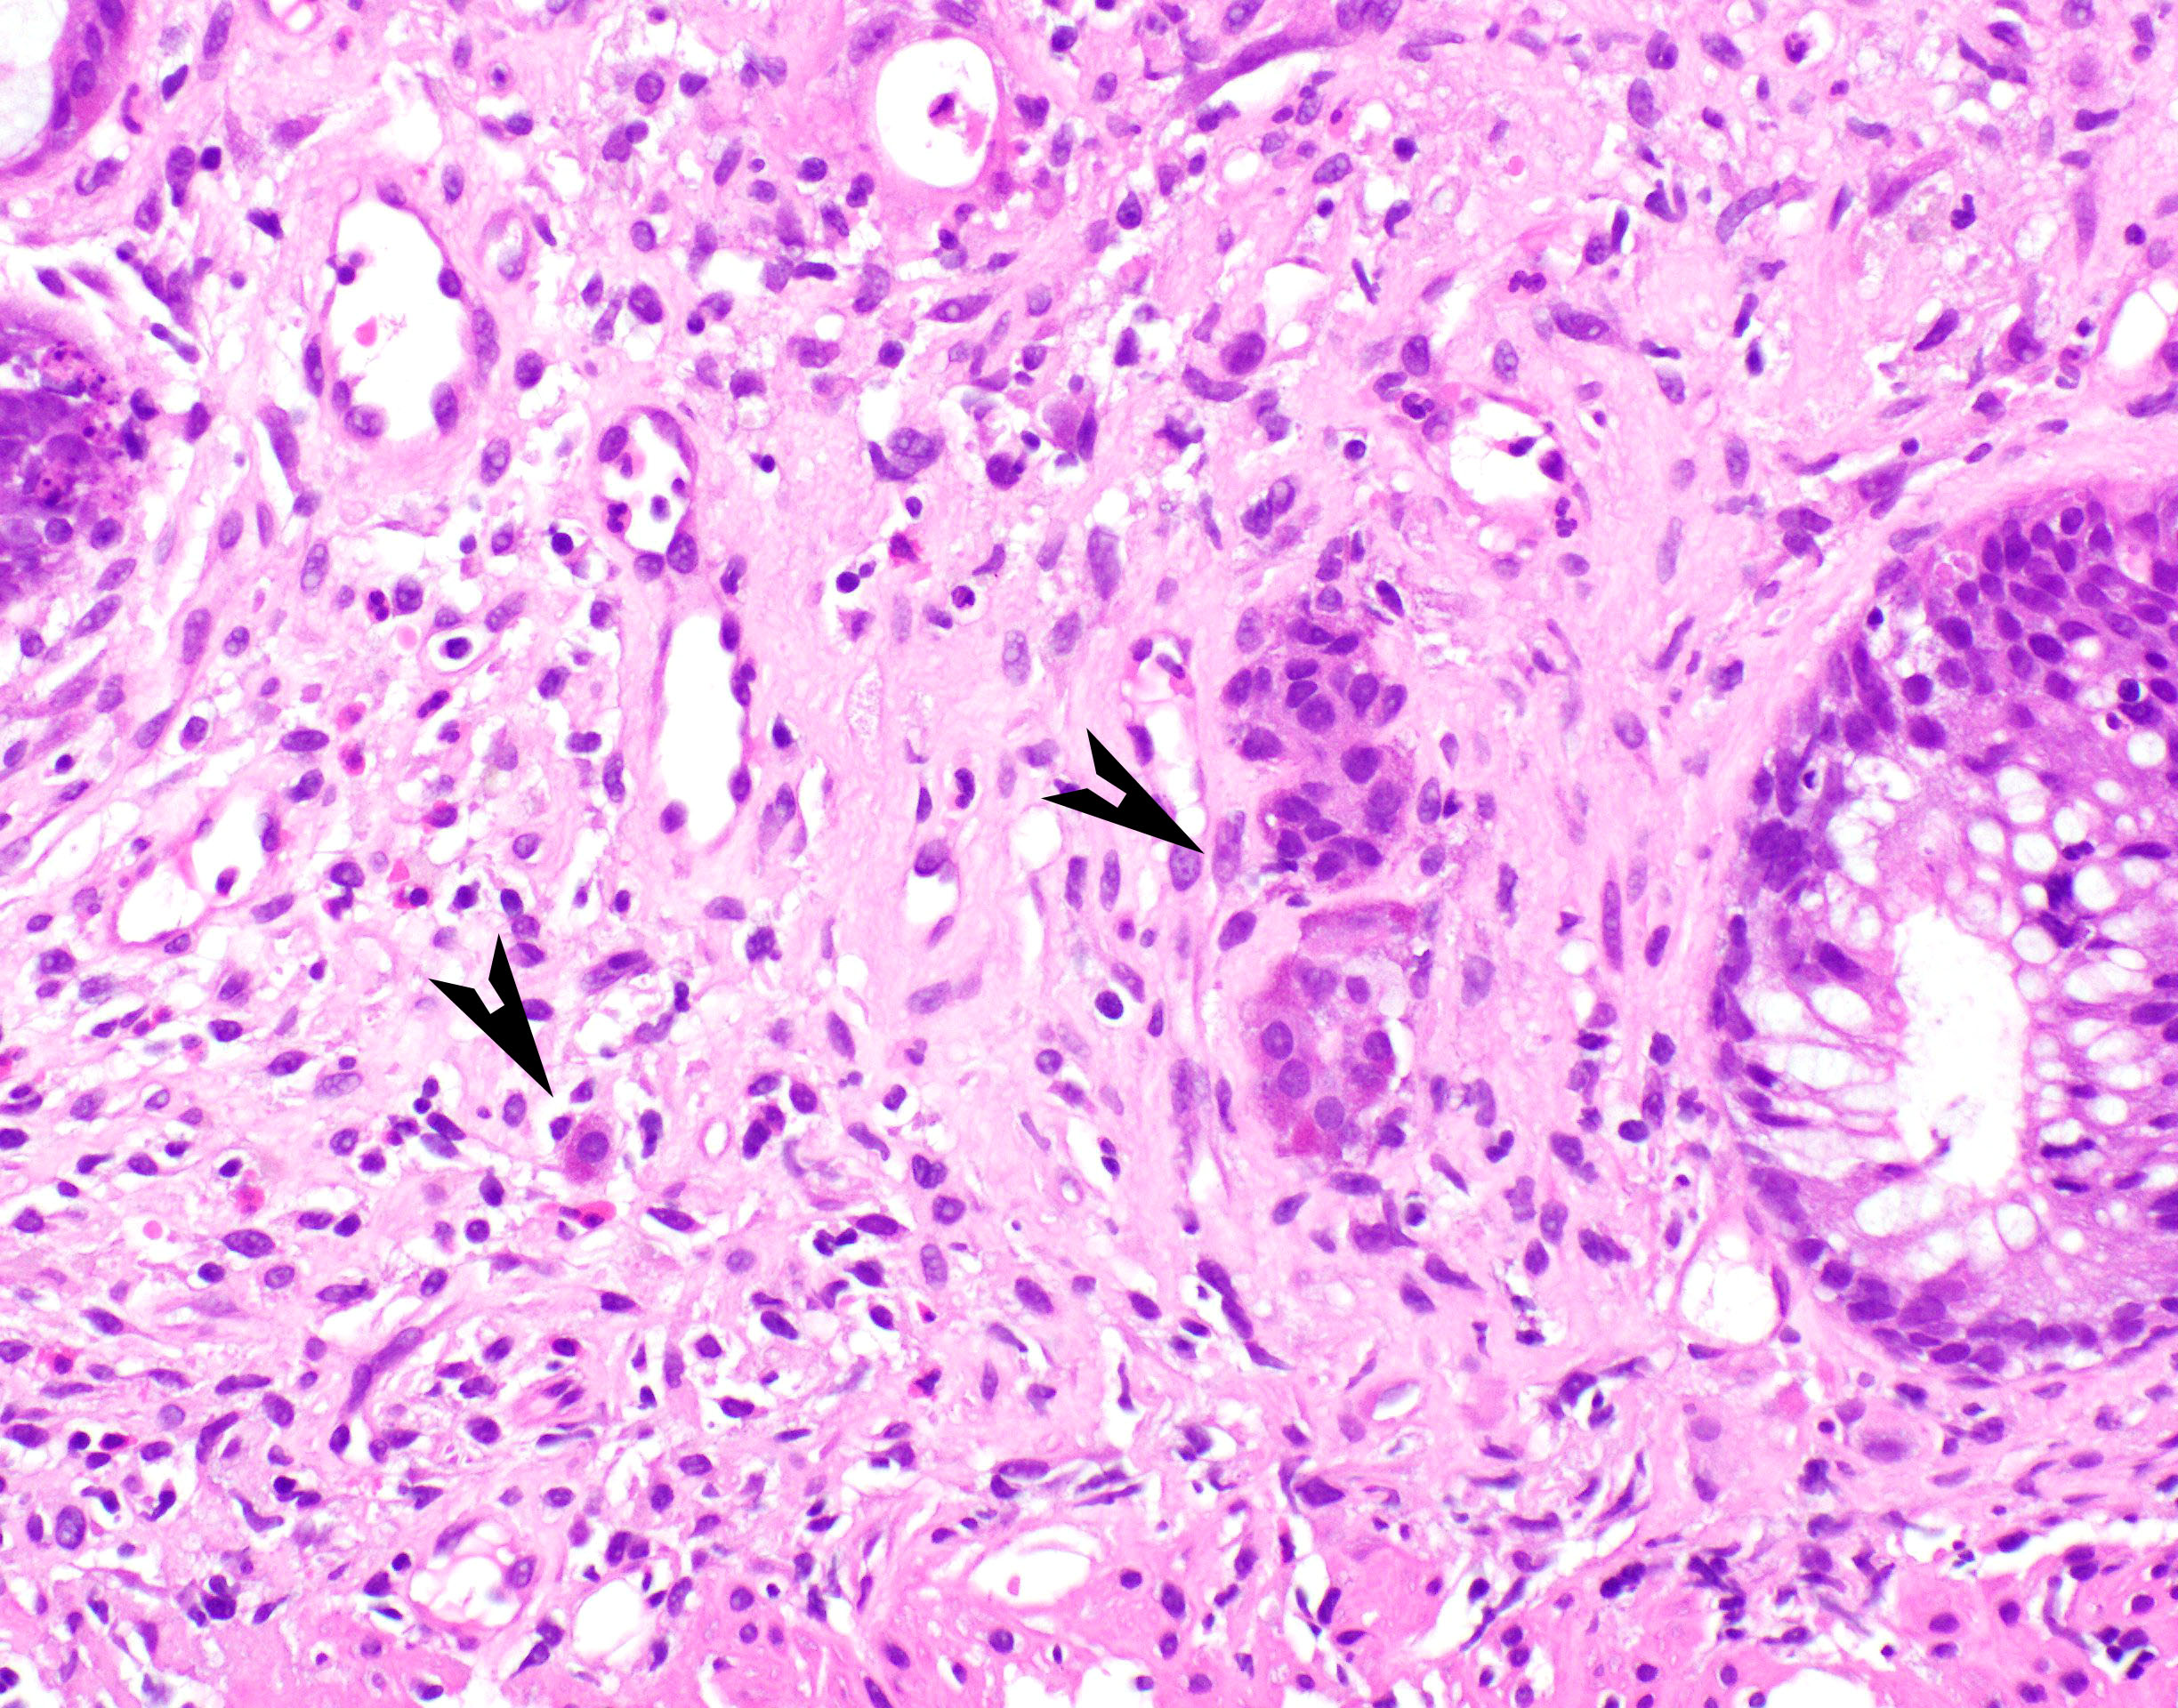

- Characteristic histologic features include crypt apoptosis, crypt dropout and ulceration (Biol Blood Marrow Transplant 2015;21:589)

- Inflammation is generally sparse

- Endocrine cell nests may be seen (Am J Surg Pathol 2013;37:1319)

- Fibrosis and crypt architectural changes are markers of longstanding disease but not specific features of chronic graft versus host disease (Am J Clin Pathol 2016;145:591)

- Apoptosis in the colon is not specific to graft versus host disease and the lower diagnostic threshold is debated

- National Institute of Health proposes ≥ 1 apoptotic body per biopsy fragment (Biol Blood Marrow Transplant 2015;21:589)

- Others propose > 6 apoptotic bodies per 10 contiguous crypts for definitive diagnosis of graft versus host disease (Am J Surg Pathol 2013;37:539)

- Cases with ≤ 6 apoptotic bodies per 10 contiguous crypts are considered indeterminate for graft versus host disease (Histopathology 2016;69:802)

- Utility of histologic grading is questionable because of poor correlation with patient outcome

- When grading is performed, the Lerner system is most commonly utilized

- Grade I: crypt apoptosis without crypt dropout

- Grade II: single crypt dropout

- Grade III: contiguous crypt dropout

- Grade IV: diffuse crypt dropout with ulceration

- When grading is performed, the Lerner system is most commonly utilized

- Graft versus host disease in autologous stem cell transplant patients shows more prominent crypt apoptosis but is otherwise histologically identical to allogeneic graft versus host disease (Mod Pathol 2018;31:1619)

- Histologic examination of at least 8 serial sections is recommended to avoid missing rare apoptotic bodies (Biol Blood Marrow Transplant 2015;21:589)